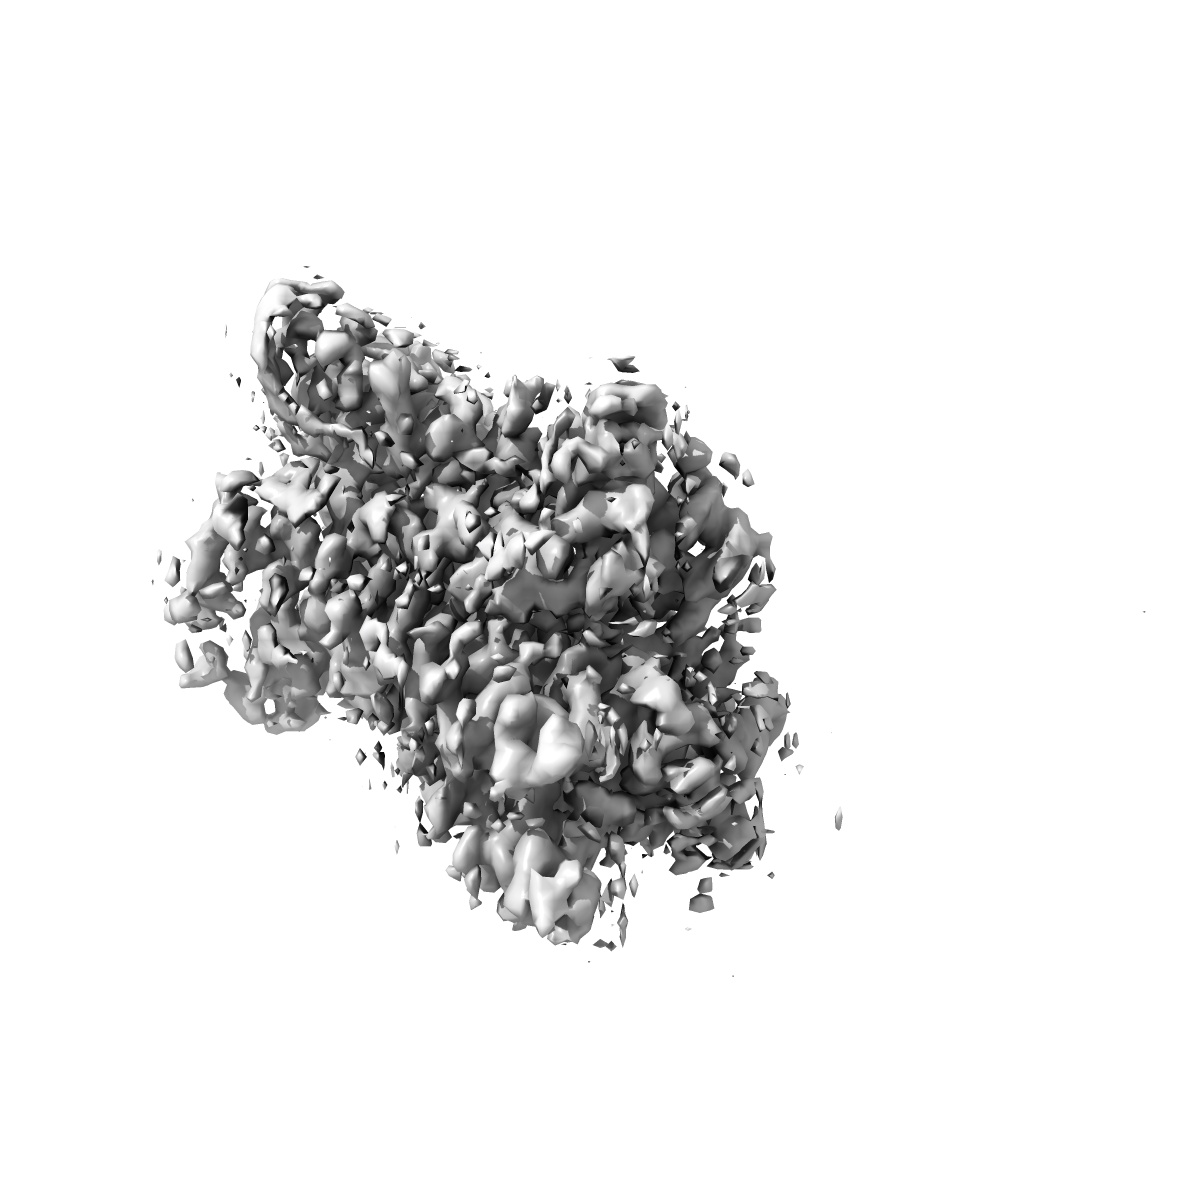

Local refinement of DRD2 bound to LSD in complex with a mini-GoA and scFv16 obtained by cryo-electron microscopy (cryoEM)

Single-particle

2.28 Å

Deposition Authors: Kim K, Gumpper RH, Fay JF, Roth BL

The polypharmacology of psychedelics reveals multiple targets for potential therapeutics.